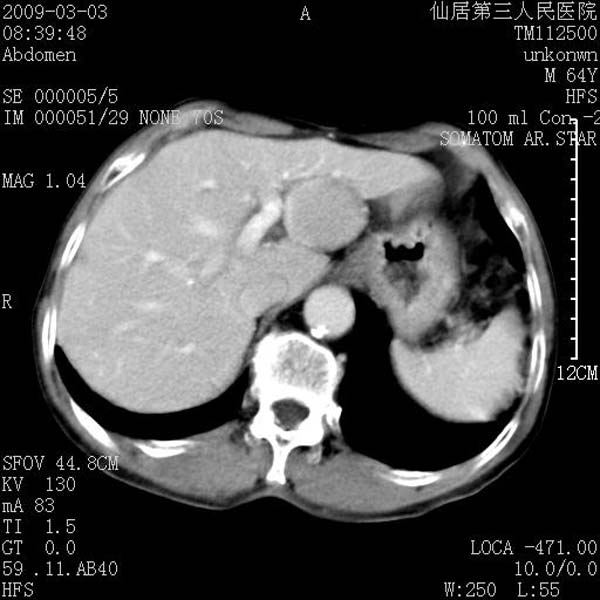

标题: CT18469:男性,64y,体检B超示肝脏低回声肿块,有胃溃疡手术 [打印本页]

患者,男性,64y,体检b超示肝脏低回声肿块,有胃溃疡手术史。

从平扫及增强的特点来看,支持肝脏腺瘤并出血。

支持肝脏腺瘤并出血。期待结果。

ct值呢?感觉没强化,象囊性。

考虑肝静脉韧带裂区良性占位性病变(囊肿?)。

考虑肝囊肿并出血可能性大.